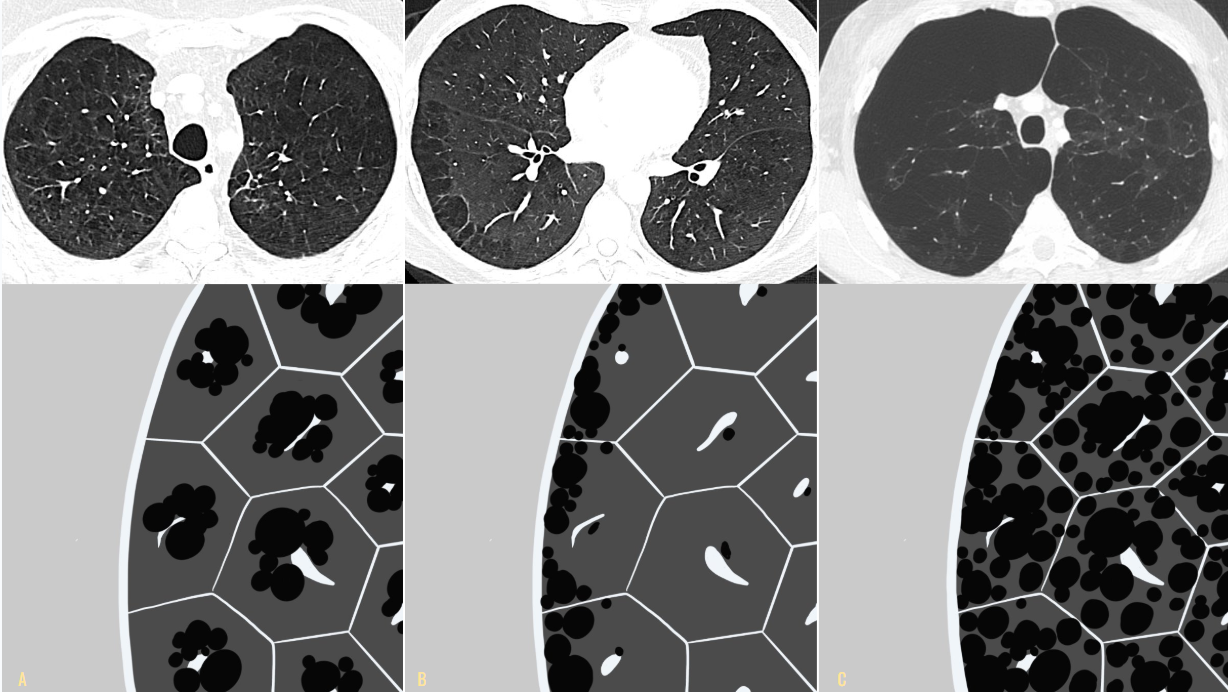

Pathologic subtypes of emphysema. A. Predominantly centriacinar emphysema. Emphysema is more severe in upper lobes. B. Predominant panacinar emphysema. Emphysema is more severe in the lower lobes.

Gross and histologic sections illustrating centriacinar A. showing holes in the center of lobules surrounded by relatively normal parenchyma. The severity varies among lobules. B. showing that the airspace enlargement is most marked adjacent to the abnormal respiratory bronchiole, corresponding to the center of the lobule. Also, some of the alveolar walls of the abnormal airspaces are thickened and fibrotic.

Gross and histologic sections illustrating panacinar emphysema C. showing how the entire lobule is uniformly affected in panacinar emphysema. D. demonstrating that the airspaces adjacent to the lobular septa are enlarged to the same degree as those in the center of the lobule.